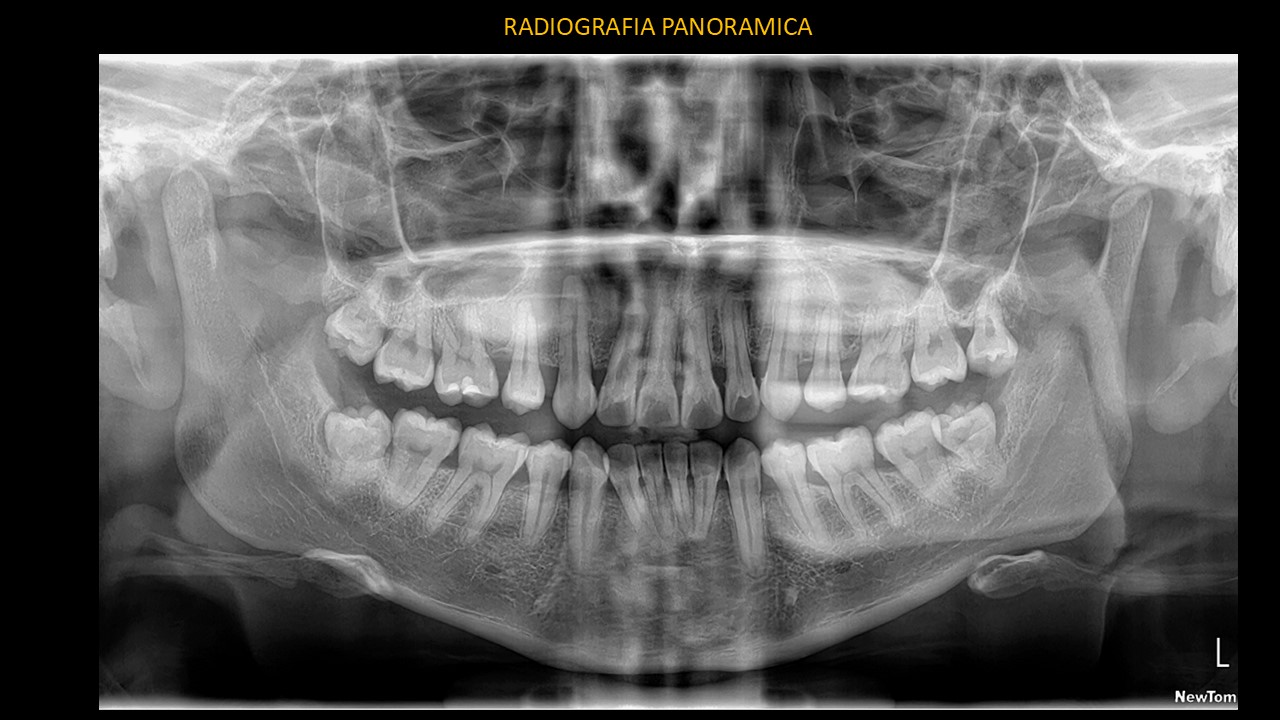

Figura 1

En la radiografía panorámica (Figura 1) se observa una imagen radiolúcida de forma irregular a nivel periapical de pieza 13 y una rarefacción radiolúcida proyectada en zona de pieza 12. En la pieza 13 se observa hipercementosis a nivel del tercio medio y apical y el ancho mesio-distal del conducto radicular de pieza 12 se encuentra aumentado. Además, se observa las piezas 38 y 48 semi incluidas con una imagen radiolúcida para coronaria compatible con probable lesión quística en formación (Quiste Paradental).